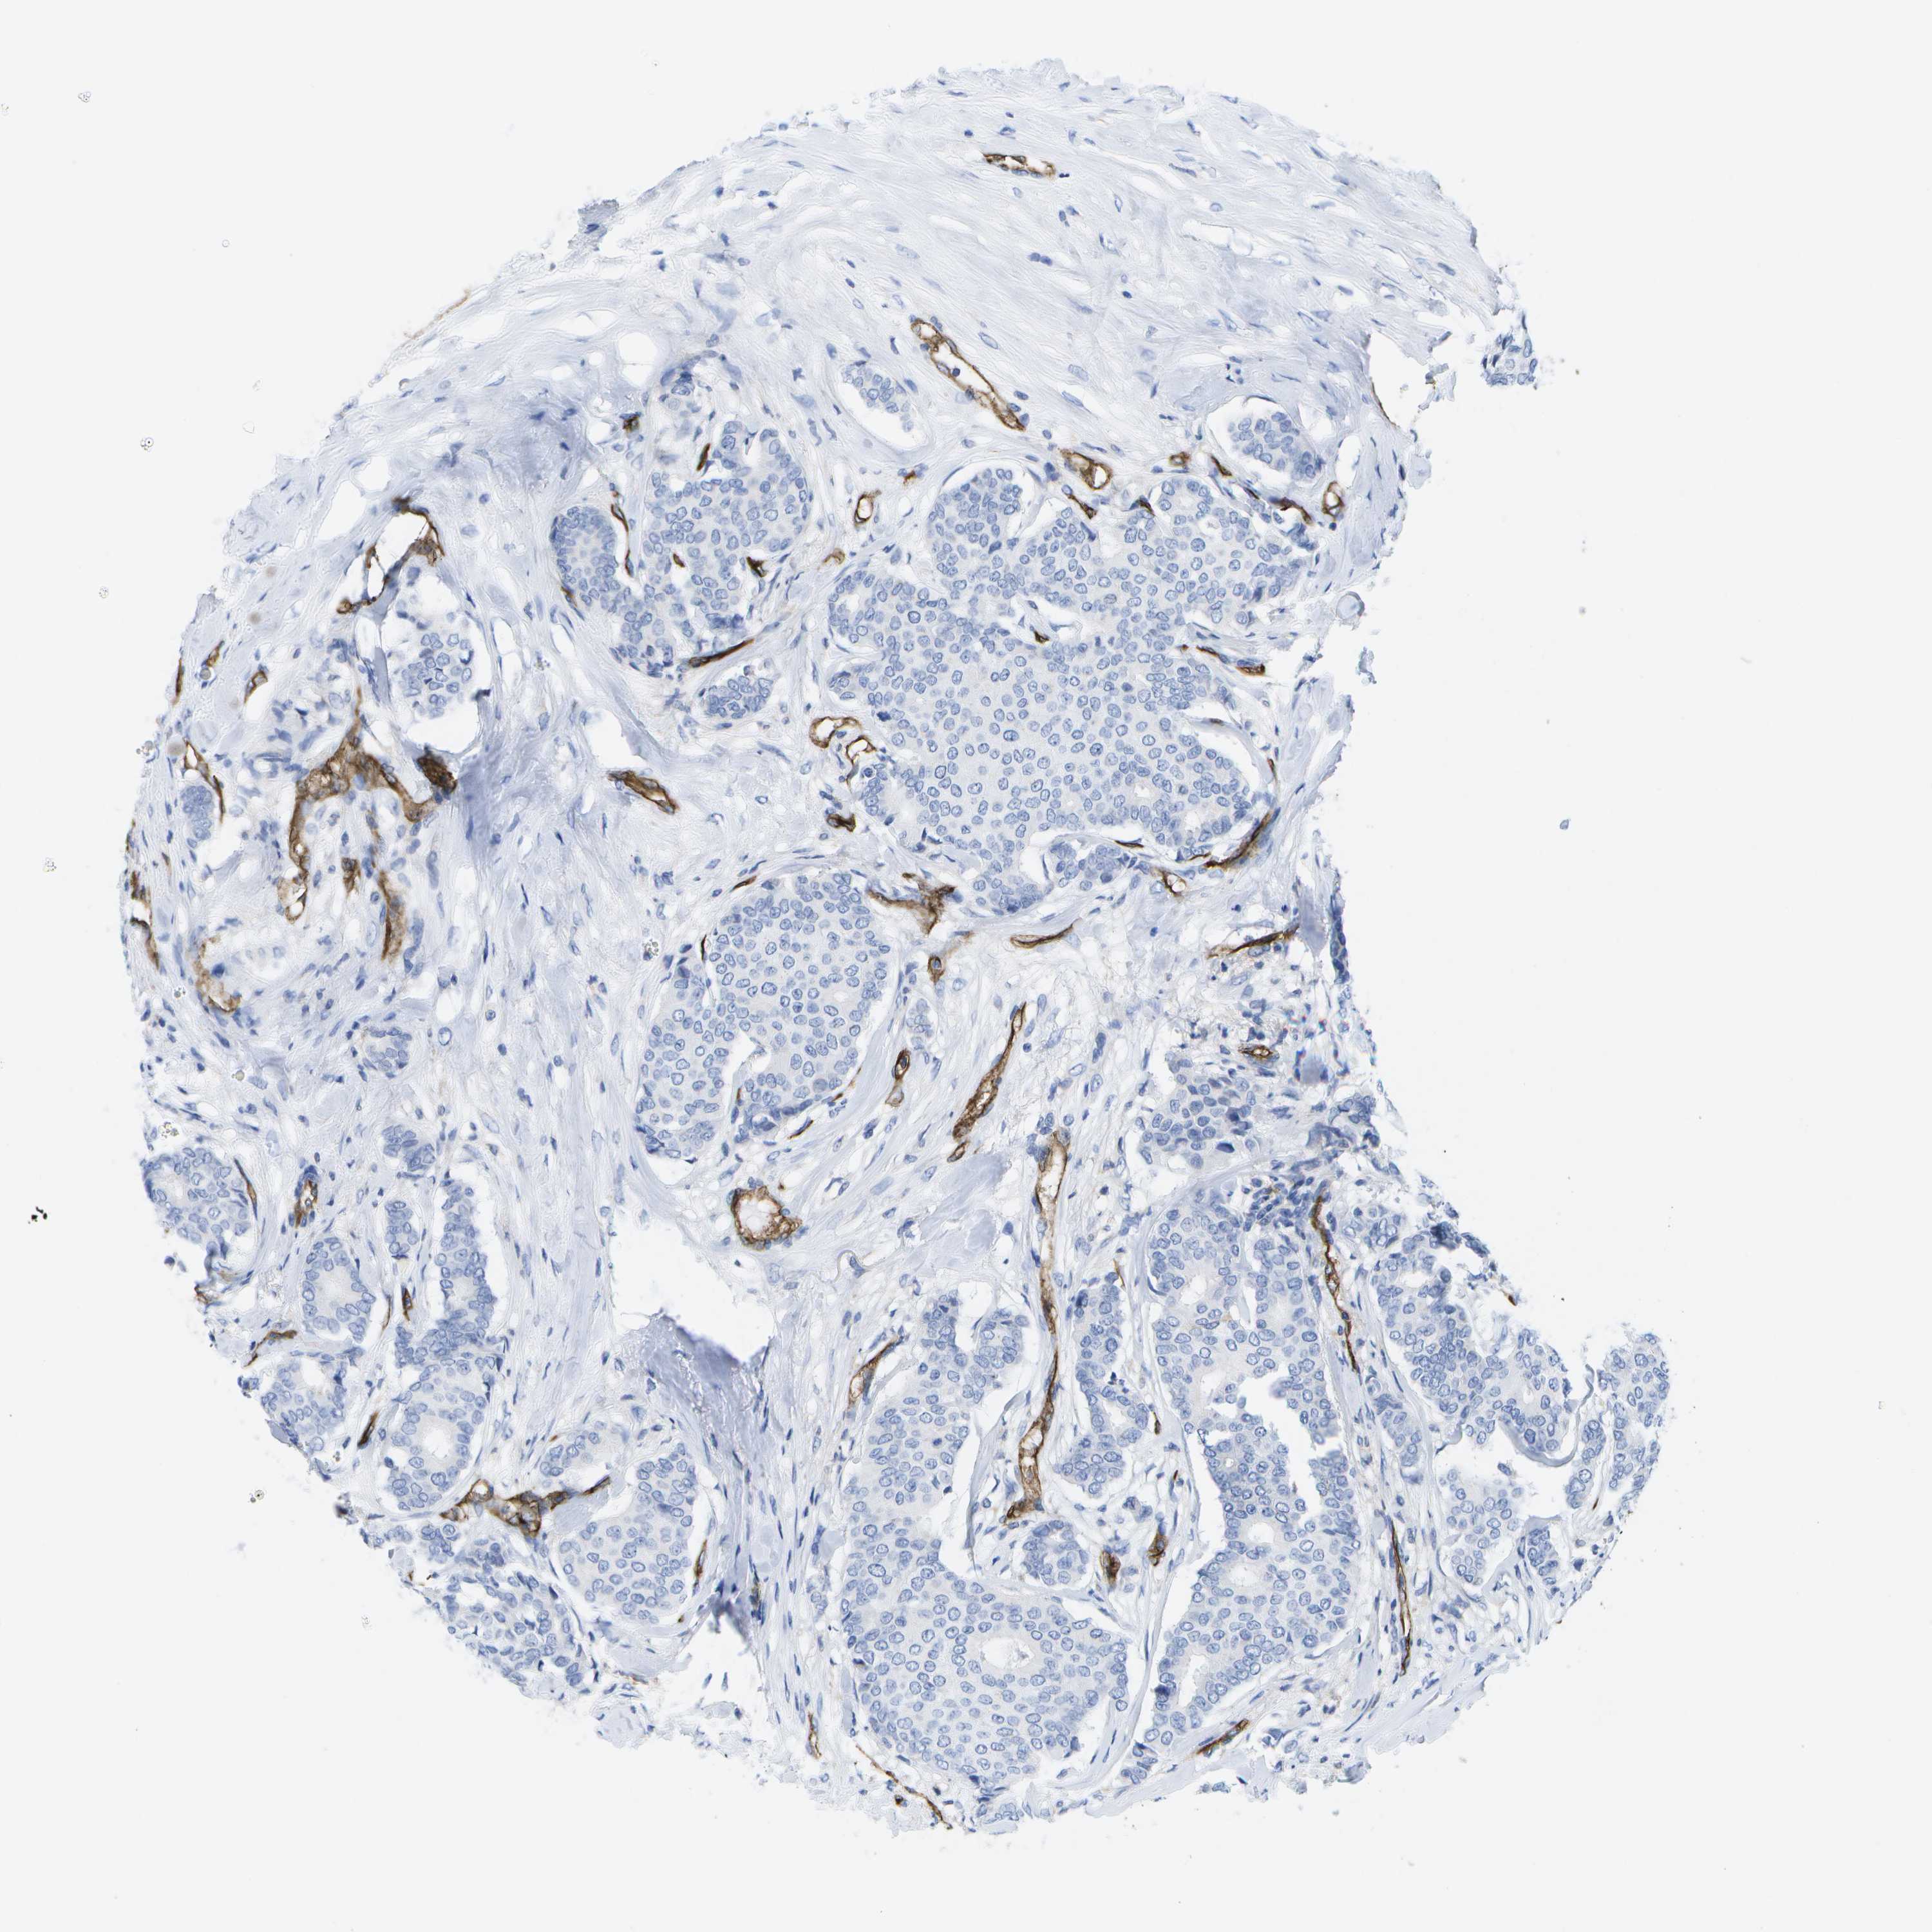

BRCA TCGA BRCA VALIDATION PROTEIN EXPRESSION

ANTIBODIES

AND

VALIDATION